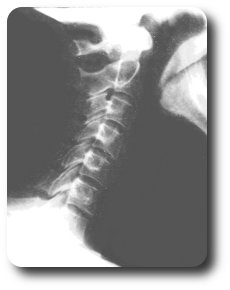

Chiropractic is a natural, drug-free, non-surgical solution to your pain problems. Chiropractic restores biomechanical function to the joints of the body, relieving nerve irritation and pain.